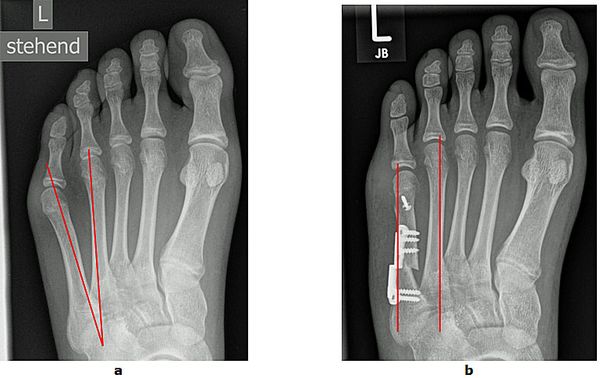

Abb.8: Korrektur des schmerzhaften Kleinzehenballen (Schneiderballen, Taylors bunion) durch die Kombination einer basisnahen Korrektur und einer Chevronette Osteotomie.

a Fehlstellungswinkel vor der Operation.

b Die Knochenachsen sind wieder parallel und der Vorfuß verschmälert.